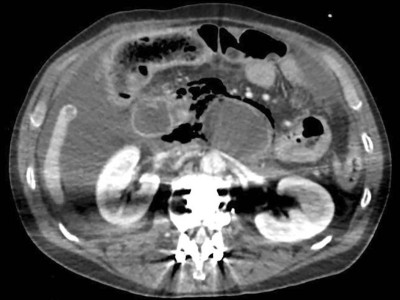

Fatale retroperitoneale nekrotisierende Fasziitis durch Aeromonas-Bakteriämie

Ein 59-jähriger Mann mit Magenkarzinom in der Vorgeschichte kommt mit schweren Schmerzen im Oberbauch in die Notaufnahme. Sein Zustand verschlechtert sich rapide. Bei der Laparotomie zeigt sich eine retroperitoneale nekrotisierende Fasziitis. Versuche, den Sepsisverlauf einzudämmen, bleiben erfolglos. Die Ursache findet sich letztendlich im nekrotischen Gewebe.

Insellappenplastik an der Nase/© Schlecht N. und Schlarb D. / all rights reserved Springer Medizin Verlag GmbH, Eine Pinzette wird vom Tisch genommen während einer OP/© JazzIRT / Getty Images / iStock (Symbolbild mit Fotomodellen), Trachealtubus/© Sherry Young / Stock.adobe.com (Symbolbild mit Fotomodell), Operation/© Alexander Lupin / Stock.adobe.com (Symbolbild mit Fotomodellen), Versorgung einer Wunde/© ARTFULLY-79 / stock.adobe.com (Symbolbild mit Fotomodell), Knochensäge im Einsatz bei Knie-TEP/© Issara / stock.adobe.com (Symbolbild mit Fotomodellen), Akute Appendizitis/© Springer Medizin, Team operiert/© HealthyShot / stock.adobe.com (Symbolbild mit Fotomodell), Eine Infusion wird platziert/© Annabell Gsödl / stock.adobe.com (Symbolbild mit Fotomodell), Wundversorgung am Unterschenkel/© Gina Sanders / stock.adobe.com, Zahn mit Karies im Zahnarztspiegel/© Сергей Кучугурный / stock.adobe.com, Bildgebung bei Appendizitis/© Reimer RP et al. / all rights reserved Springer Medizin Verlag GmbH, Oberflächliche Wundinfektion nach elektiver Relaparotomie/© Mueller-Elmau T & Friess H / all rights reserved Springer Medizin Verlag GmbH, Operation am Fuß/© เลิศลักษณ์ ทิพชัย / Stock.adobe.com (Symbolbild mit Fotomodellen), Dünndarmileus, retroperitoneale freie Luft und Aszites im CT/© Al Hossain Al Nour. et al. / all rights reserved Springer Medizin Verlag GmbH, Hyperpigmentierung der palmaren Handlinien bei 16-jähriger Patientin mit Morbus Addison/© Manske J et al. doi.org/10.1007/s00112-023-01850-3 unter CC-BY 4.0, Blutstropfen auf Handschuh/© Brandy Sites / Hemera / Thinkstock, Chirurgin hält Nadel/© virojt / stock.adobe.com (Symbolbild mit Fotomodell), Hand mit Hundebiss/© Dr. P. Marazzi / Science Photo Library, Wundbehandlung bei einem diabetischen Fuß/© kirov1969 / stock.adobe.com (Symbolbild mit Fotomodell), Kaiserschnittnarbe/© Jun / Getty Images / iStock (Symbolbild mit Fotomodell), Chirurgin und Assistentin bei OP/© Georgiy / stock.adobe.com (Symbolbild mit Fotomodellen), Search Icon, Senior und Rollstuhl auf Flur/© Peter Atkins / stock.adobe.com (Symbolbild mit Fotomodellen)